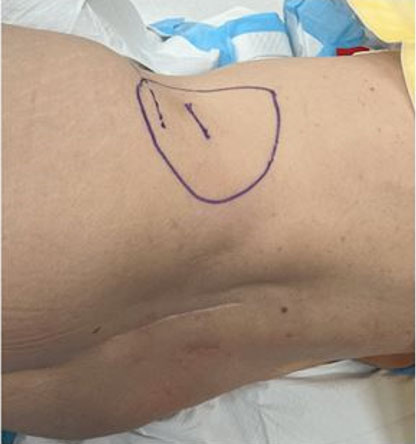

The hernia site was marked preoperatively with the patient standing (Figure 2). General anesthetic was administered. The patient was placed in the left lateral position and the bed broken to widen the 12th rib and iliac crest distance. An incision was made parallel and superior the right iliac crest. With retraction and dissection, the defect was located. The edges of the hernial defect were defined with retraction and dissection in a circumferential fashion. The pre-peritoneal space was entered, and a large pocket created with a combination of blunt and sharp dissection. The peritoneum and pre-peritoneum were separated widely across the iliac blade and muscles anterior and posterior (Figure 3). A bard Ventrio hernia mesh (11×14 cm) was placed in the pre-peritoneal space with at least 5 cm overlap (Figure 4). The mesh was secured inferiorly with endo tackers to the iliac blade. The wound was closed in layers including the defect. No drain was placed.

Figure 2: Case 1—Preoperative marking of right lumbar hernia.